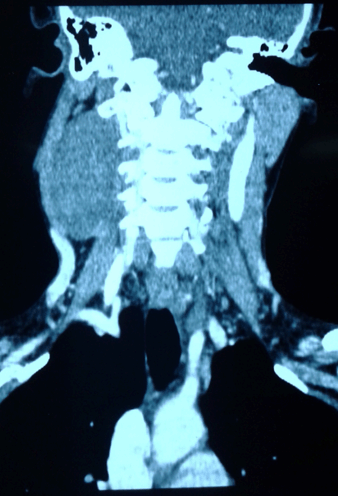

Ultrasound of the neck showed a well-defined solid soft tissue mass with internal vascularity. Contrast enhanced computed tomography scan confirmed a 3.6x3.2x6.9 cm hypodense mass with no contrast enhancement. The lesion was in-between right internal and external carotid artery and extending to the base of the skull. Right internal jugular vein was displaced anteriorly. Right common carotid artery (R/CCA) was stretched (Figure 1).

Figure 1: Computed tomography scan of right sided hypodense mass with no contrast enhancement.